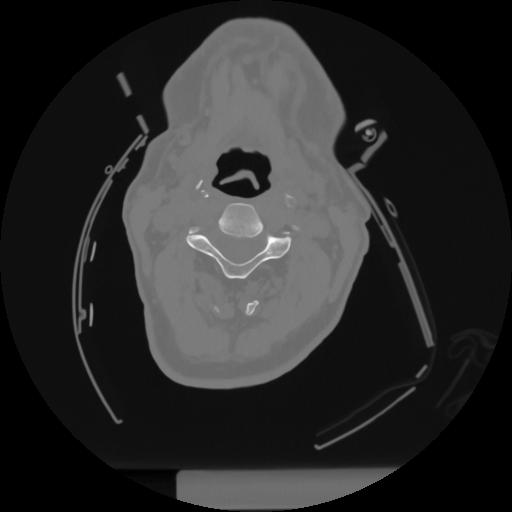

12 P.BLANDAS,,Vol,0.5,P.BLANDAS,,